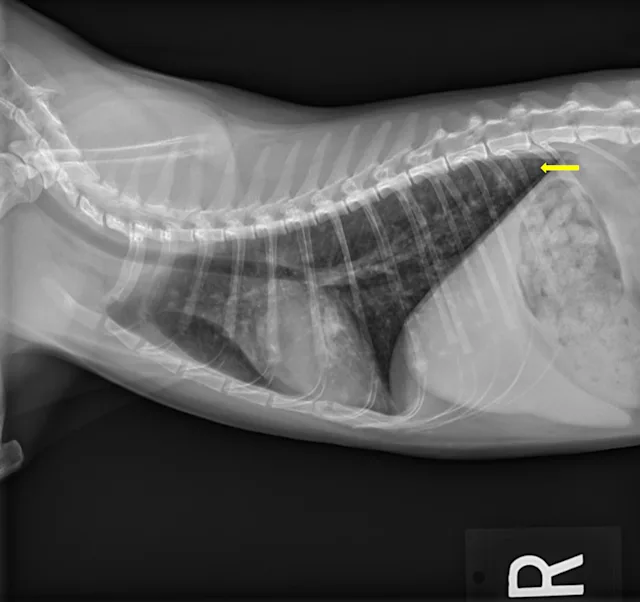

At the 2-month recheck, continued clinical improvement was observed. The owner reported Eleanor was doing well at home. Her body weight had increased to 8.3 lb (3.8 kg); BCS was 4/9.On physical examination, mildly increased bronchovesicular sounds were still present. Fundic examination results were normal. Thoracic radiographs showed continued improvement; remaining lesions were predominantly in the peripheral lung field with a more caudodorsal distribution (Figure 3).

A

FIGURE 3 Left lateral (A), right lateral (B), and ventrodorsal (C) thoracic radiographs 2 months after initiation of itraconazole. Remaining lesions (arrows) were predominantly in the peripheral lung field with a more caudodorsal distribution.